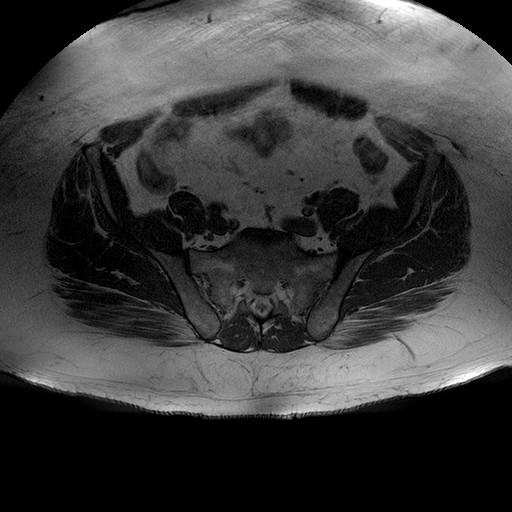

Esami: RMN BACINO

T1W_TSE

Evidenti e simmetriche alterazioni osteofitosiche in regione coxo femorale con riduzione delle rime articolari. Degenerazione completa del cercine glenoideo. Non attuali segni di versamento articolare. Non segni di edema osseo che escludono attuale algodistrofia od osteonecrosi. Lieve e simmetrica riduzione del trofismo della muscolatura glutea.